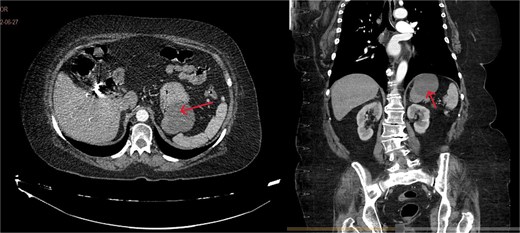

A 71-year-old female with a history of systemic arterial hypertension and dyslipidemia under treatment, with previous laparoscopic cholecystectomy and total abdominal hysterectomy. No other relevant medical history. She presented to the emergency department with gastrointestinal symptoms of 2 months' evolution, including postprandial abdominal pain, nausea, and vomiting, resulting in oral intolerance, which required hospital admission. The physical examination was unremarkable. During her stay in the emergency department, various imaging studies were performed, and the computed tomography (CT) scan revealed a hypodense lesion measuring 66 × 50 × 58 mm with thin gastric walls (Fig. 1).

Contrast-enhanced CT, transverse, and coronal sections. Arrows: gastric duplication cyst. A slight displacement of the stomach is observed, without spleen involvement and independent from the pancreas.